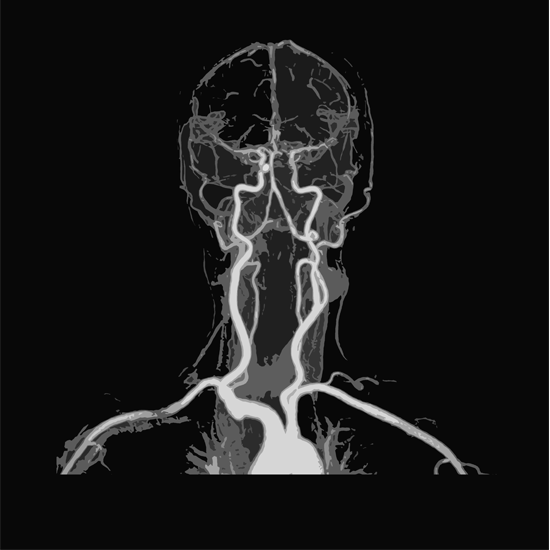

MRA (Magnetic resonance angiography) of the brain and neck is used to create 3D images of the blood vessels in the neck and brain region. This scan is usually recommended to determine the blood flow in the arteries, abnormalities, and blockage in the blood vessels.

• This scan is used to get clear pictures of blood vessels in the brain and neck.

• It helps the doctor in identifying the flow of blood in arteries.

• It detects and diagnoses aneurysms, blockages, vascular conditions, and any abnormalities in blood vessels of both the neck and brain.

• Examine the carotid arteries.

• Assess the cerebral vessels in the brain

• Examine both healthy and diseased vessels in the brain and neck

• Diagnose abnormal widening or ballooning of a cerebral vessel